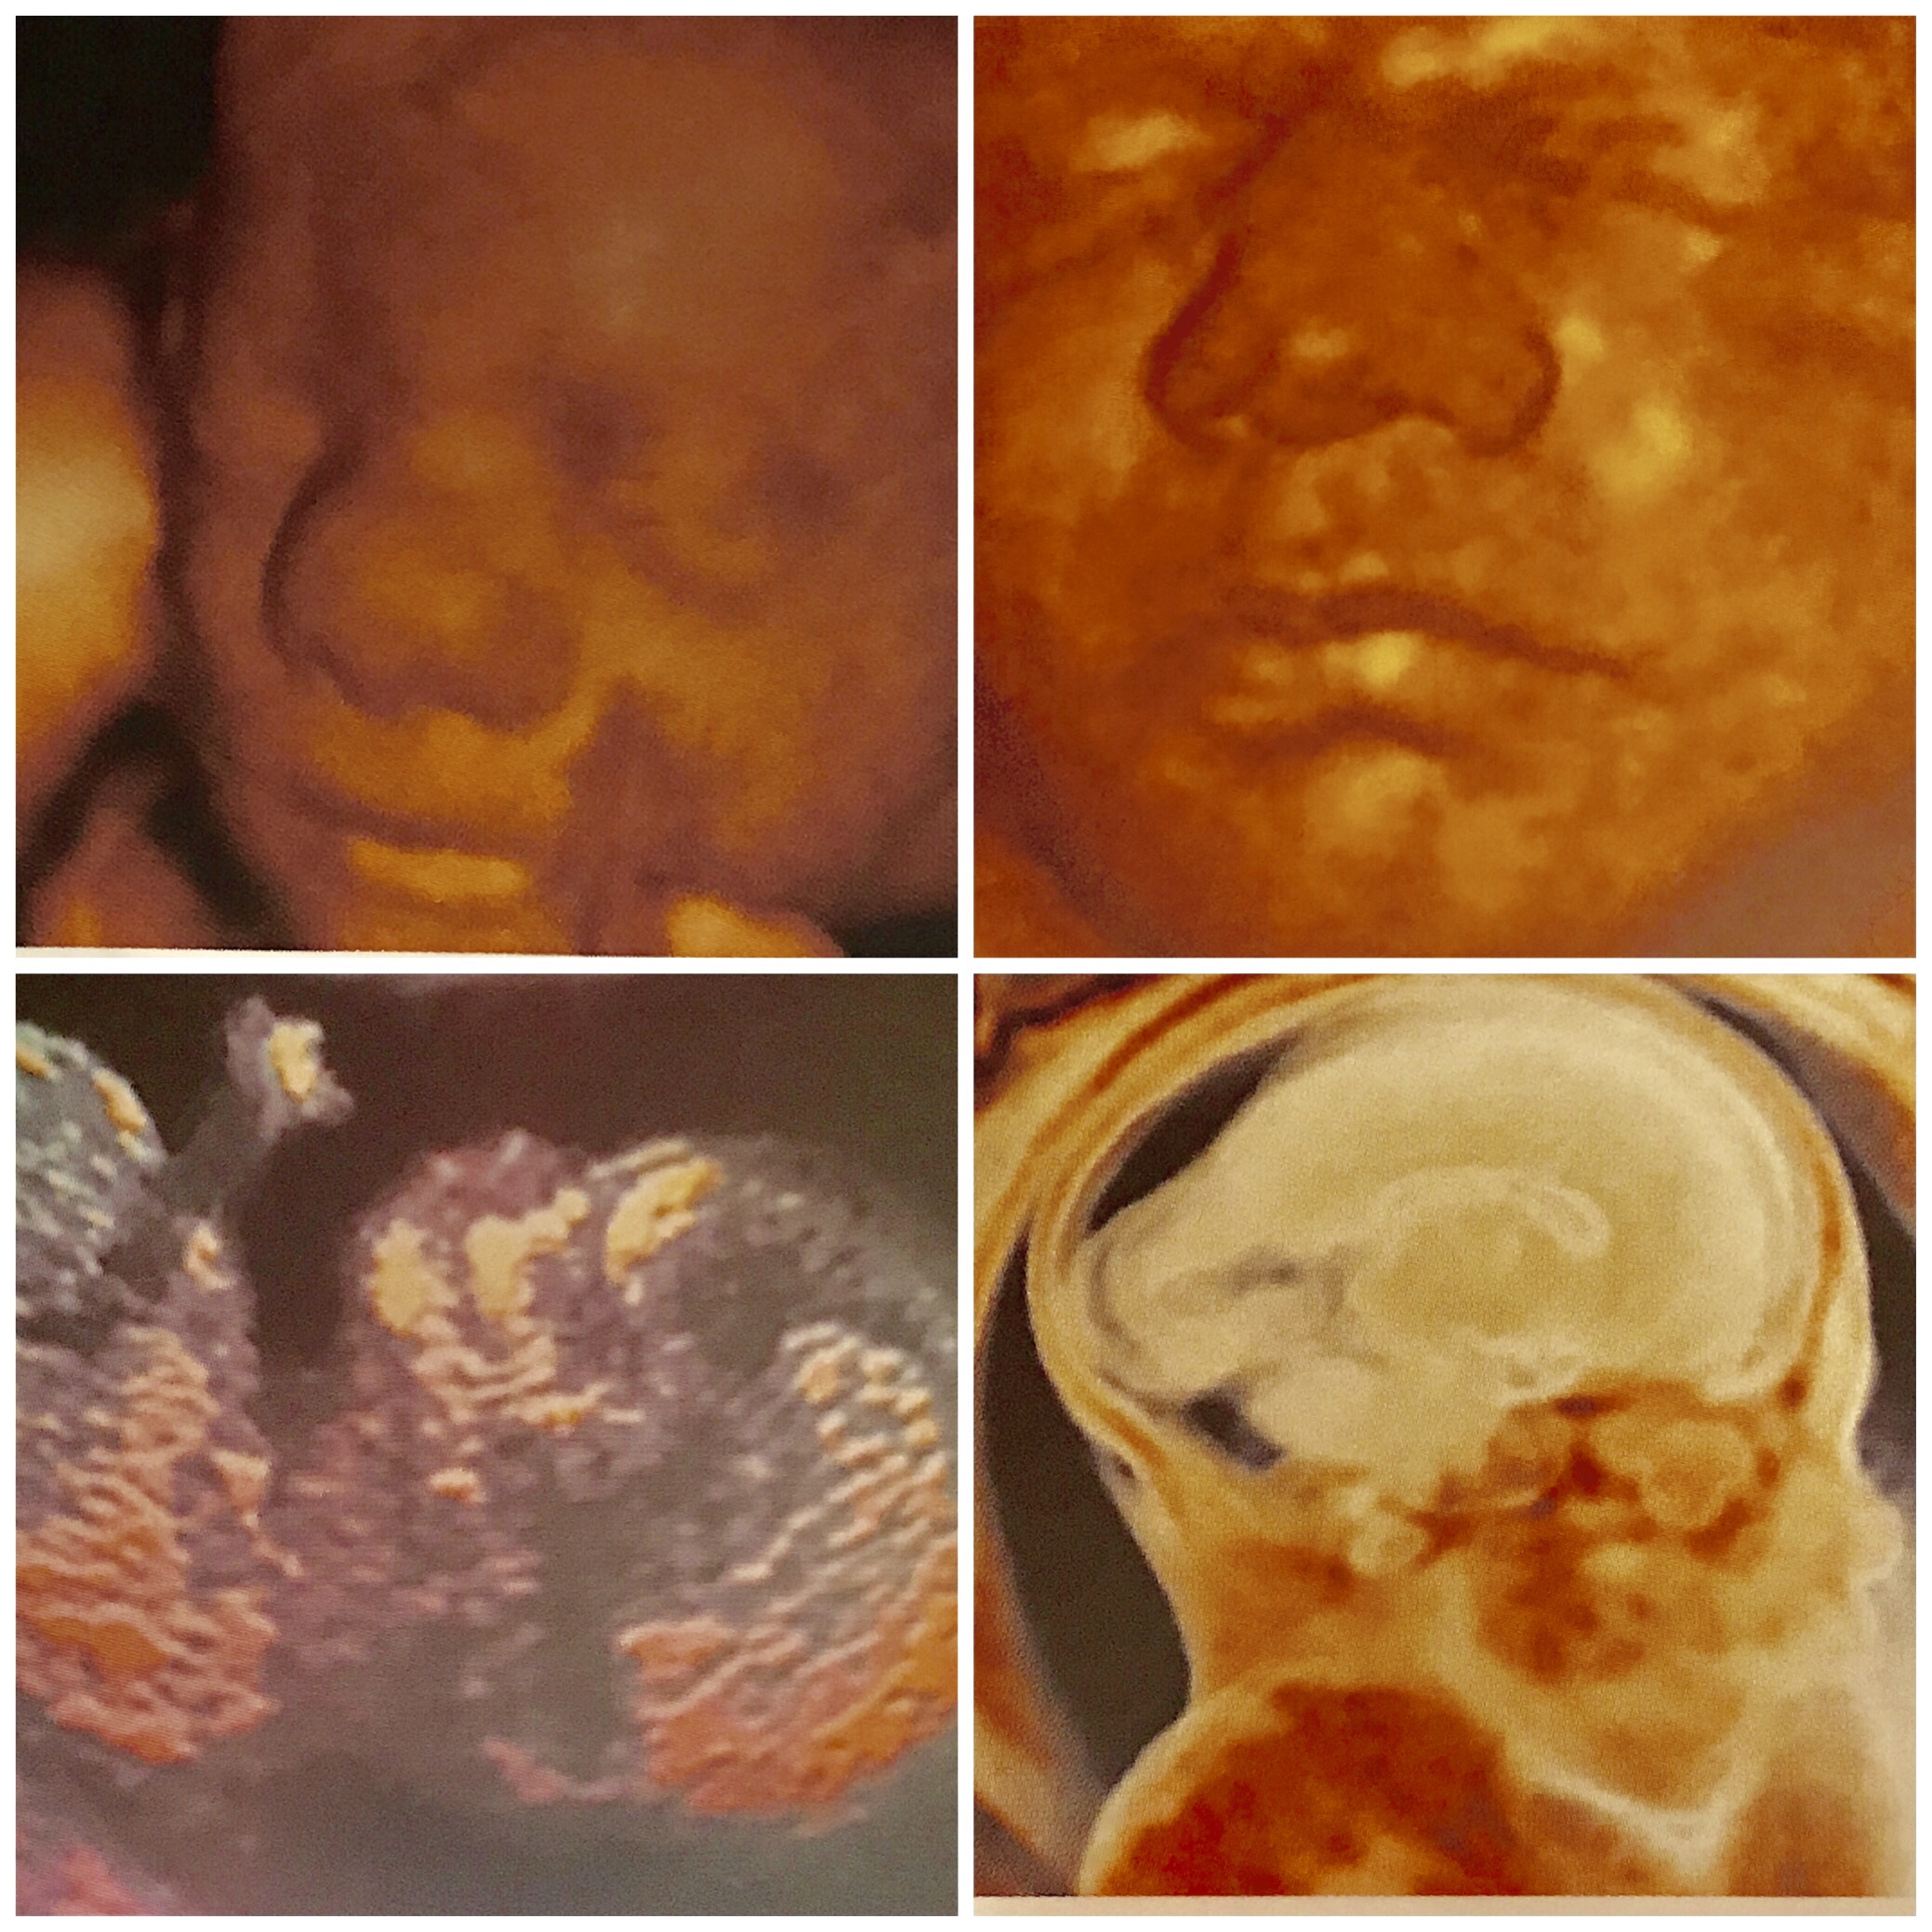

As of today, our baby is 35 weeks, the size of a pineapple according to the Bump and the smaller (in most cases) honeydew melon according to Baby Center. At this stage the baby should be about 18 inches long and 5 1/4 pounds (a bit bigger than Dr. C estimated on my appointment on Friday). This will be one of many weeks in which s/he will be putting on even more weight though his or her length may not change greatly.

This new weight is in the form of baby fat which is for insulation and protection.

According to The Bump his or her hearing is now fully developed. This makes sense as s/he has been very active moving around to background music at work. Still, at his or her larger size moves like somersaults are out and kicks and rolling movements are still possible.

At this point baby would have five weeks left of development, but with a planned Cesarean section before that, my baby will be getting only to the term date of 39 weeks. I cannot believe we will be meeting our child so very soon.